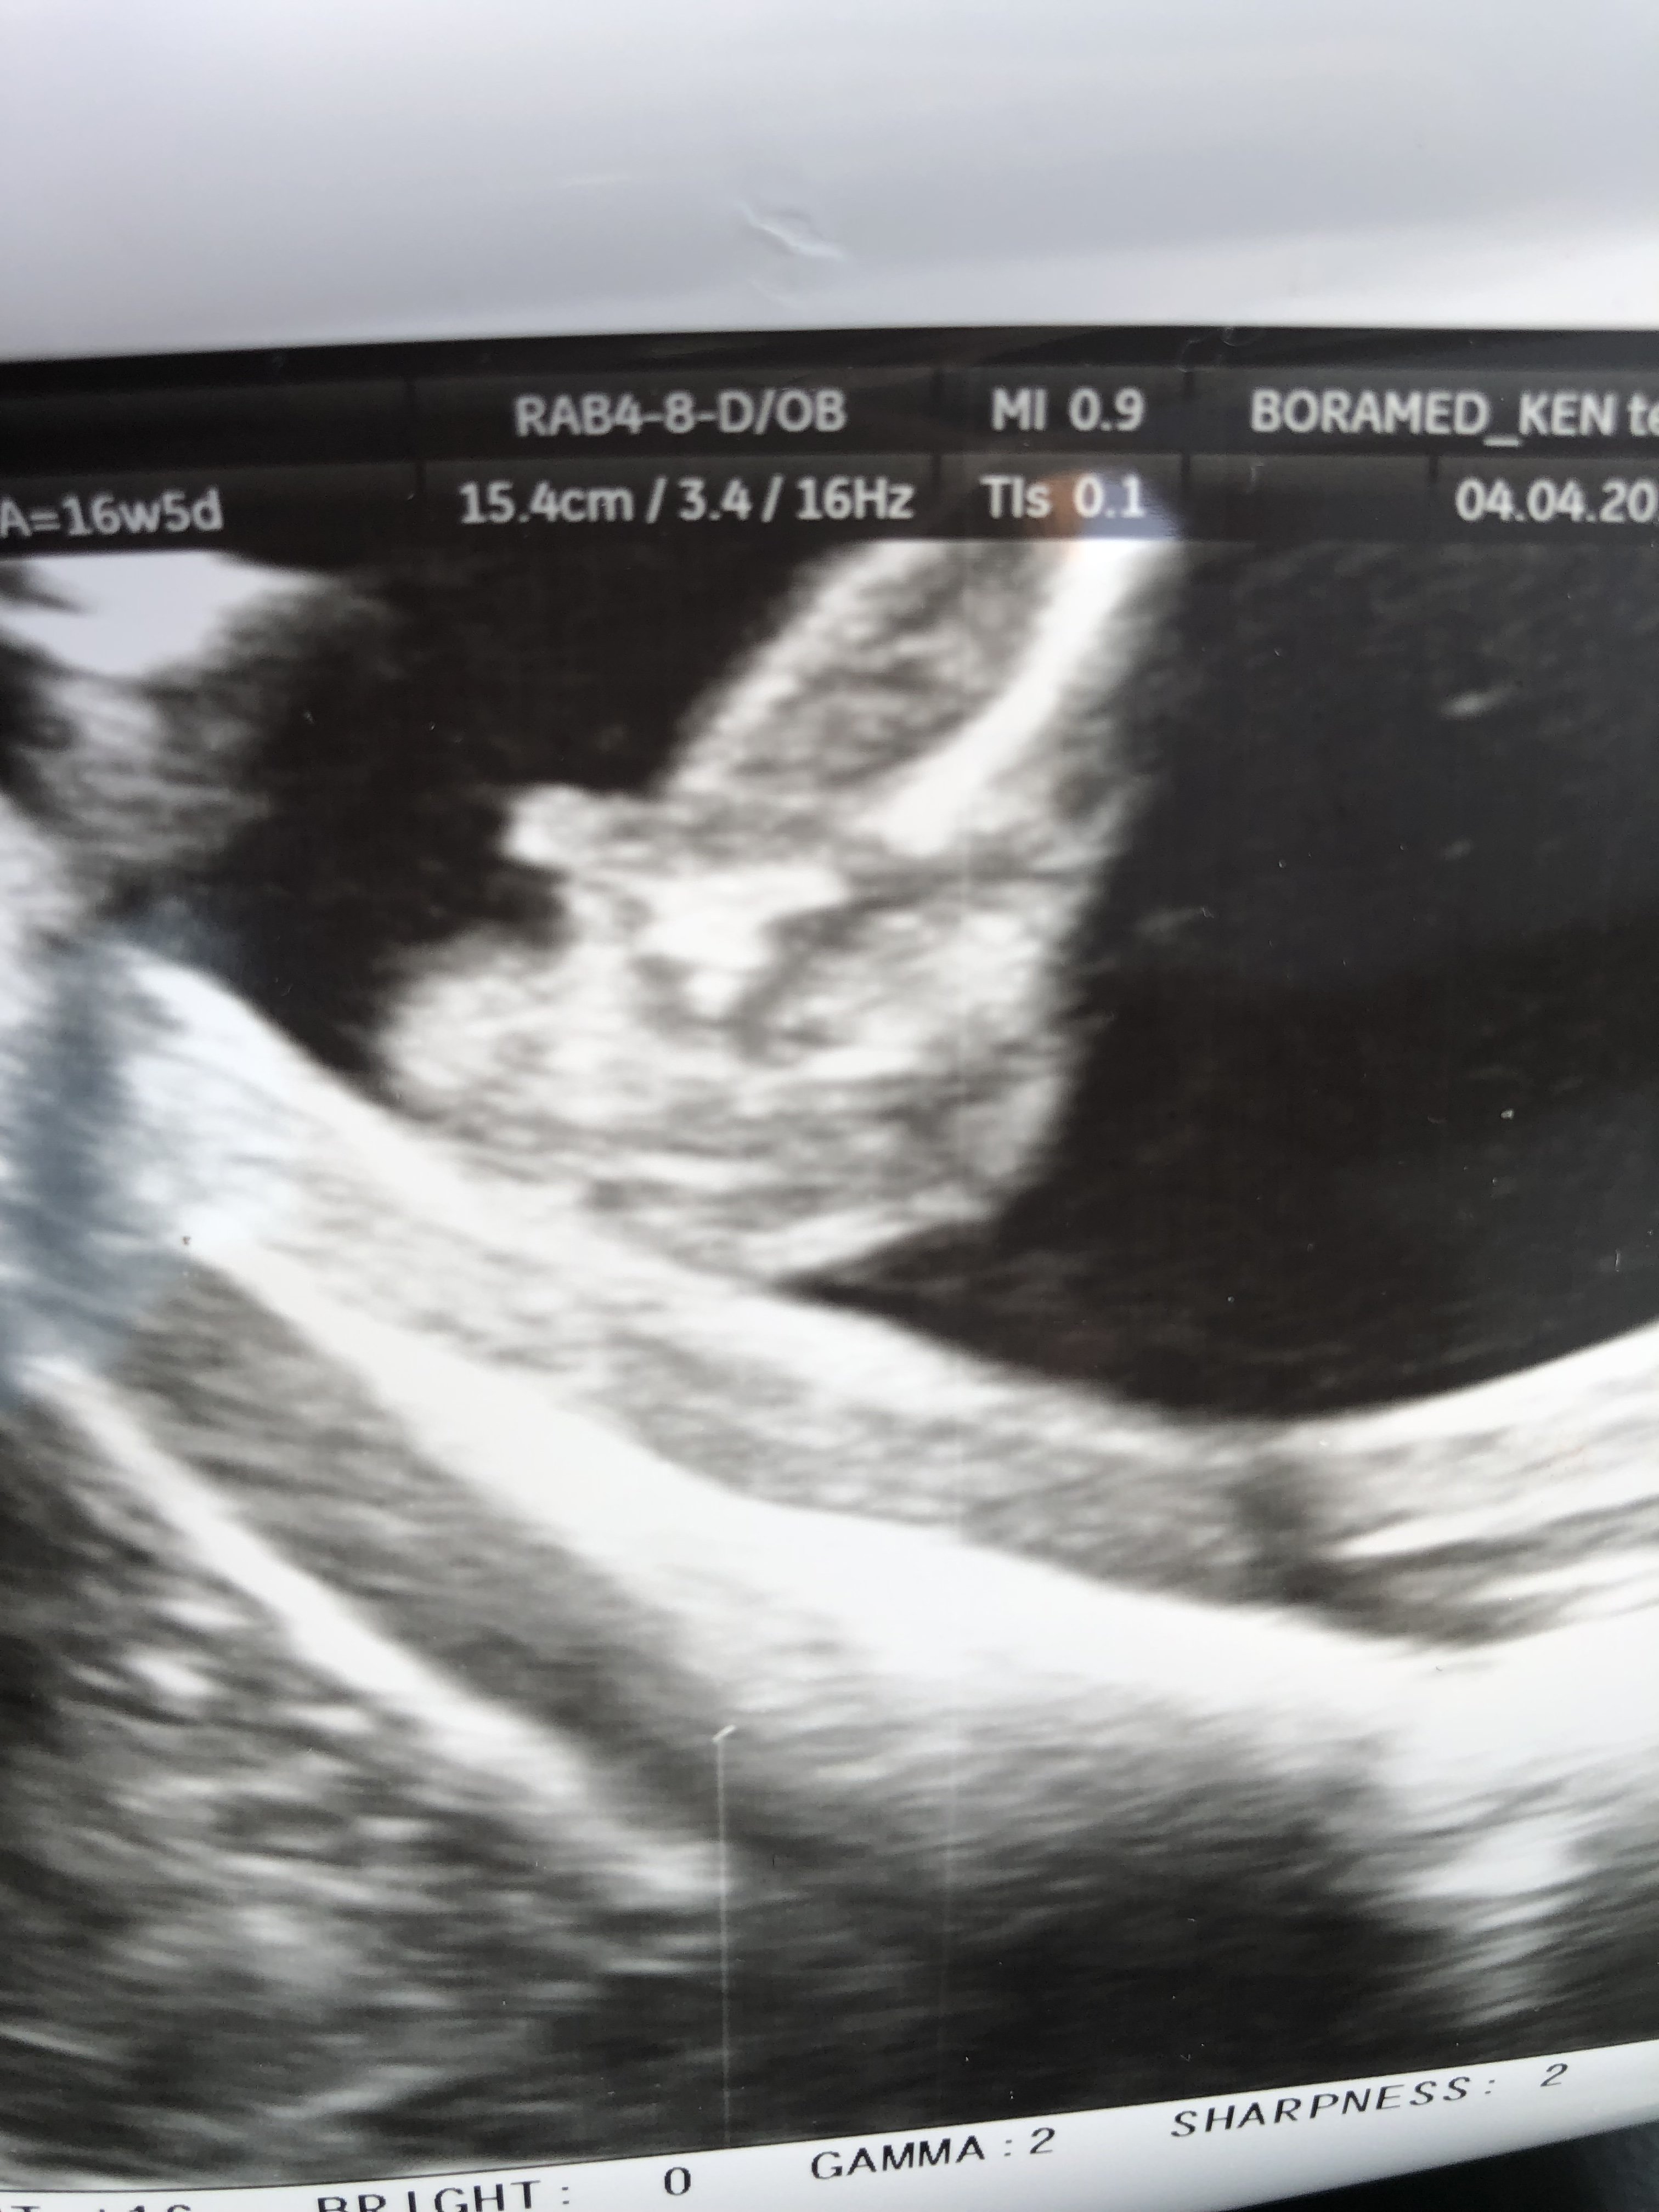

Cześć dziewczyny proszę was o ocenę zdjęcia usg... Miesiąc temu zapowiedzieli mi syna a 4 grudnia na połówkowym ze córka... Trochę mam mętlik w głowie 😞

I czy ten „cypelek”na nubie o czymś świadczy czy maja go zarówno chłopcy jak i dziewczynki

Zżera mnie ciekawość, choć gdzieś w środku czuje ze druga córa się szykuje zamiast synka...

• E622F8B3-4E12-4F76-A34E-879251B1E76F.jpeg

E622F8B3-4E12-4F76-A34E-879251B1E76F.jpeg

295,3 KB · Wyświetleń: 416